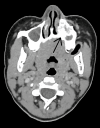

Ewing sarcoma (ES) is a small, round, blue cell malignant neoplasm that rarely occurs in the craniofacial skeleton, with presentation in the maxilla being exceedingly rare. We report the case of a 14-year-old girl with a two-year history of slowly progressive facial swelling that has recently become greatly enlarged. Imaging revealed an aggressive expansile left maxillary lesion with soft-tissue involvement and internal calcifications. Surgical resection was performed, and histopathological analysis showed sheets of homogenous round cells with minimal cytoplasm and round nuclei. Immunohistochemical staining for CD99, CD56, and NKX2.2 was positive, while staining for epithelial, muscle, and neural markers was negative, thereby confirming the diagnosis of ES. This case highlights the diagnostic difficulty of ES in unusual sites such as the maxilla, where it can mimic odontogenic or fibro-osseous lesions. Early diagnosis with histopathology and immunohistochemistry is important for appropriate management, which usually includes surgical resection followed by chemotherapy.